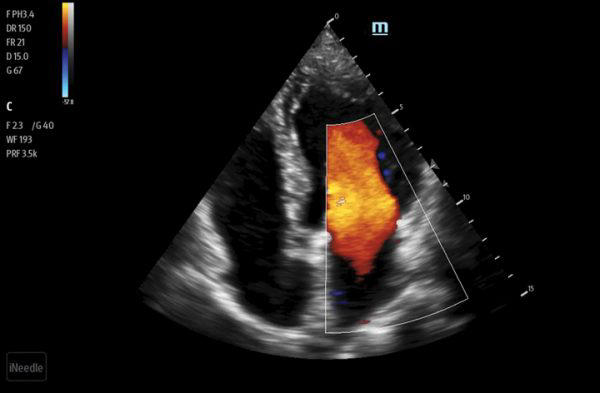

Clinical Images